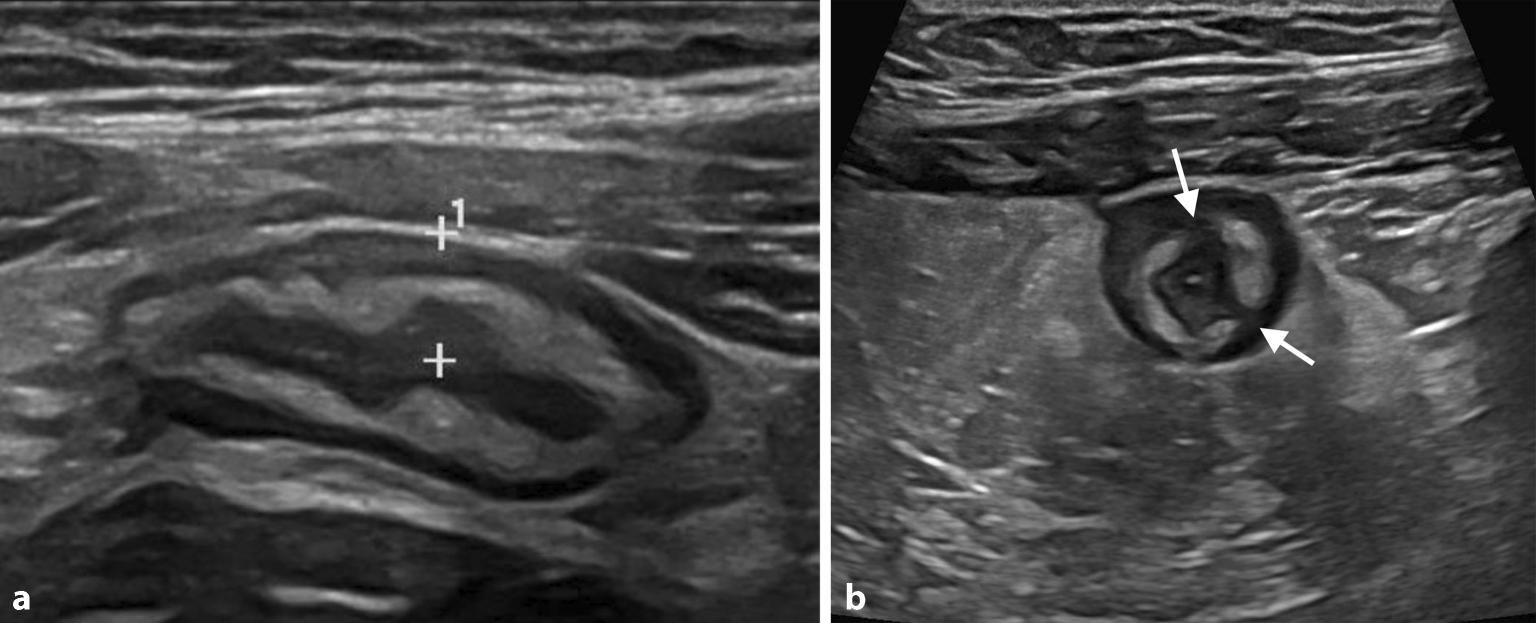

Des Weiteren wird auf die Wandstratifizierung, die Darstellbarkeit aller Wandschichten und auf umliegende Strukturen (Fettimbibierung, vergrößerte Lymphknoten, freie Flüssigkeit) geachtet (Abb. 3).

Abb. 3

Die Sonographie zeigt eine deutliche Wandverdickung auf > 3 mm (a, Distanzmarken) mit einer Verdickung der echoreichen Submukosa mit fokalen hypoechogenen Unterbrechungen der Schichtung (b, Pfeile), hinweisend auf das Vorliegen einer aktiven Entzündung